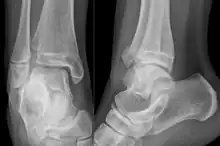

![]() | |

| Fracture of both sides of the ankle with dislocation as seen on anteroposterior X-ray. (1) fibula, (2) tibia, (arrow) medial malleolus, (arrowhead) lateral malleolus | |